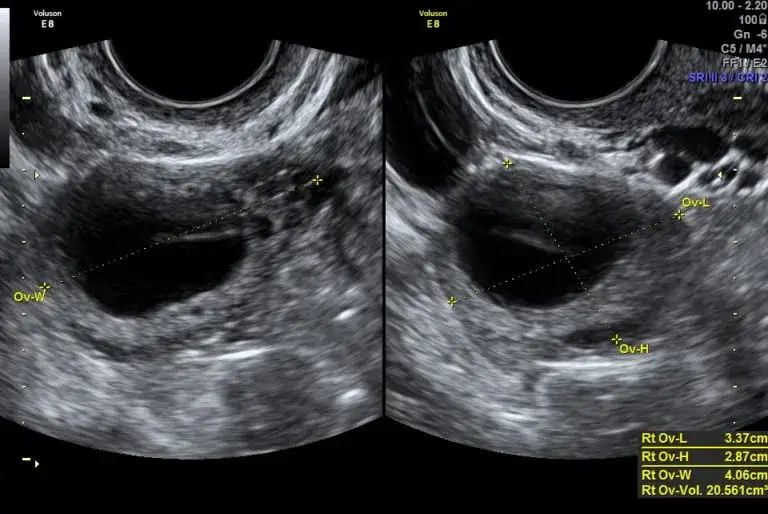

Monitoring u ginekologa (USG): Kiedy potrzebujesz 100% pewności?

W sytuacjach, gdy domowe metody okazują się niewystarczające lub gdy para ma problemy z zajściem w ciążę, najbardziej precyzyjną metodą potwierdzenia owulacji jest monitoring cyklu za pomocą badania USG u ginekologa. Lekarz może obserwować wzrost pęcherzyka dominującego, a następnie potwierdzić jego pęknięcie i uwolnienie komórki jajowej. Jest to metoda, która daje niemal 100% pewności i jest często zalecana w diagnostyce niepłodności oraz w trakcie leczenia wspomaganego rozrodu.